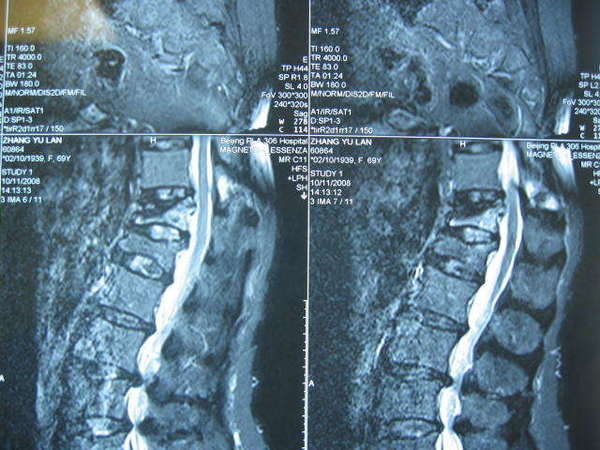

女性,69岁,腰背疼痛8个月,早期卧床2周后症状减轻,开始下地行走,虽然症状逐渐缓解但仍有反复加重,尤其是翻身、起坐、站立和行走时明显,平素多是卧床,摊扶上卫生间等,严重影响患者日常生活。查体发现患者胸腰段明显后凸畸形及压叩痛,活动明显受限,不愿起坐和站力。检查X片发现腰1、胸12两个椎体压缩骨折,MRI检查发现腰1骨折为陈旧性并已愈合,胸12骨折未愈合,有明显的渗出现象,是造成目前存在症状的原因。入院诊断:胸12压缩骨折,腰1压缩骨折(陈旧性)。

术前MRI(压脂)片----T12存在深出信号,L1信号正常